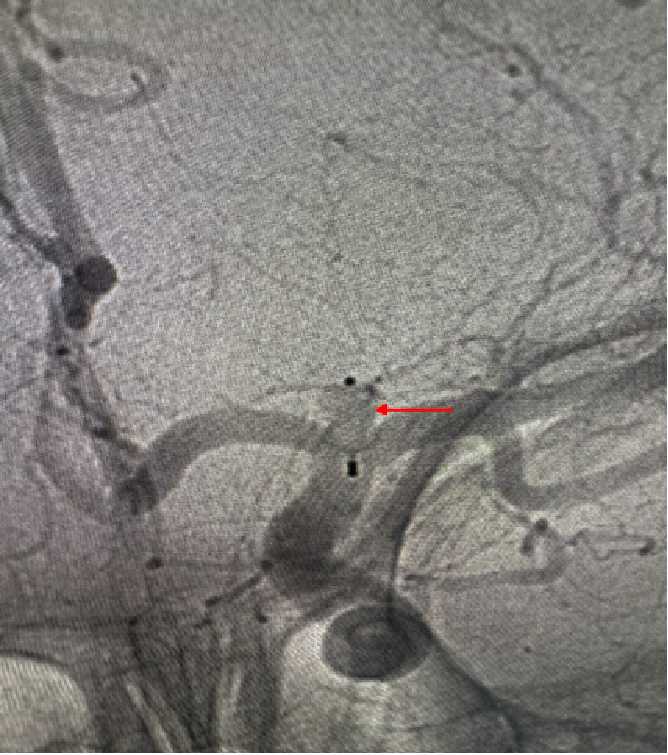

许刚副主任在仔细研究过患者的病历及影像资料后,建议患者早期行手术治疗,给出了患者三个治疗方案,开颅夹闭手术,常规弹簧圈加支架介入栓塞手术,而最后一种,则是目前最先进的方式WEB™植入术。经过详细告知和沟通,患者家属最终选择了行WEB™植入手术。于是在充分完善术前准备后,在影像介入室、麻醉科以及屈满莉护师的全力配合下,许刚副主任、张明副主任医师在全麻下为患者施行了大脑中动脉瘤内扰流装置WEB植入术,因为有之前的手术经验,手术过程十分顺利,仅用时15分钟就完成了WEB植入,术中即刻造影显示动脉瘤内造影剂滞留明显,其余左侧大脑中动脉、大脑前动脉等血管均通畅。患者术后顺利苏醒,拔管后未诉特殊不适,言语功能及肢体功能均未受影响。2天后患者出院。

术中植入WEB